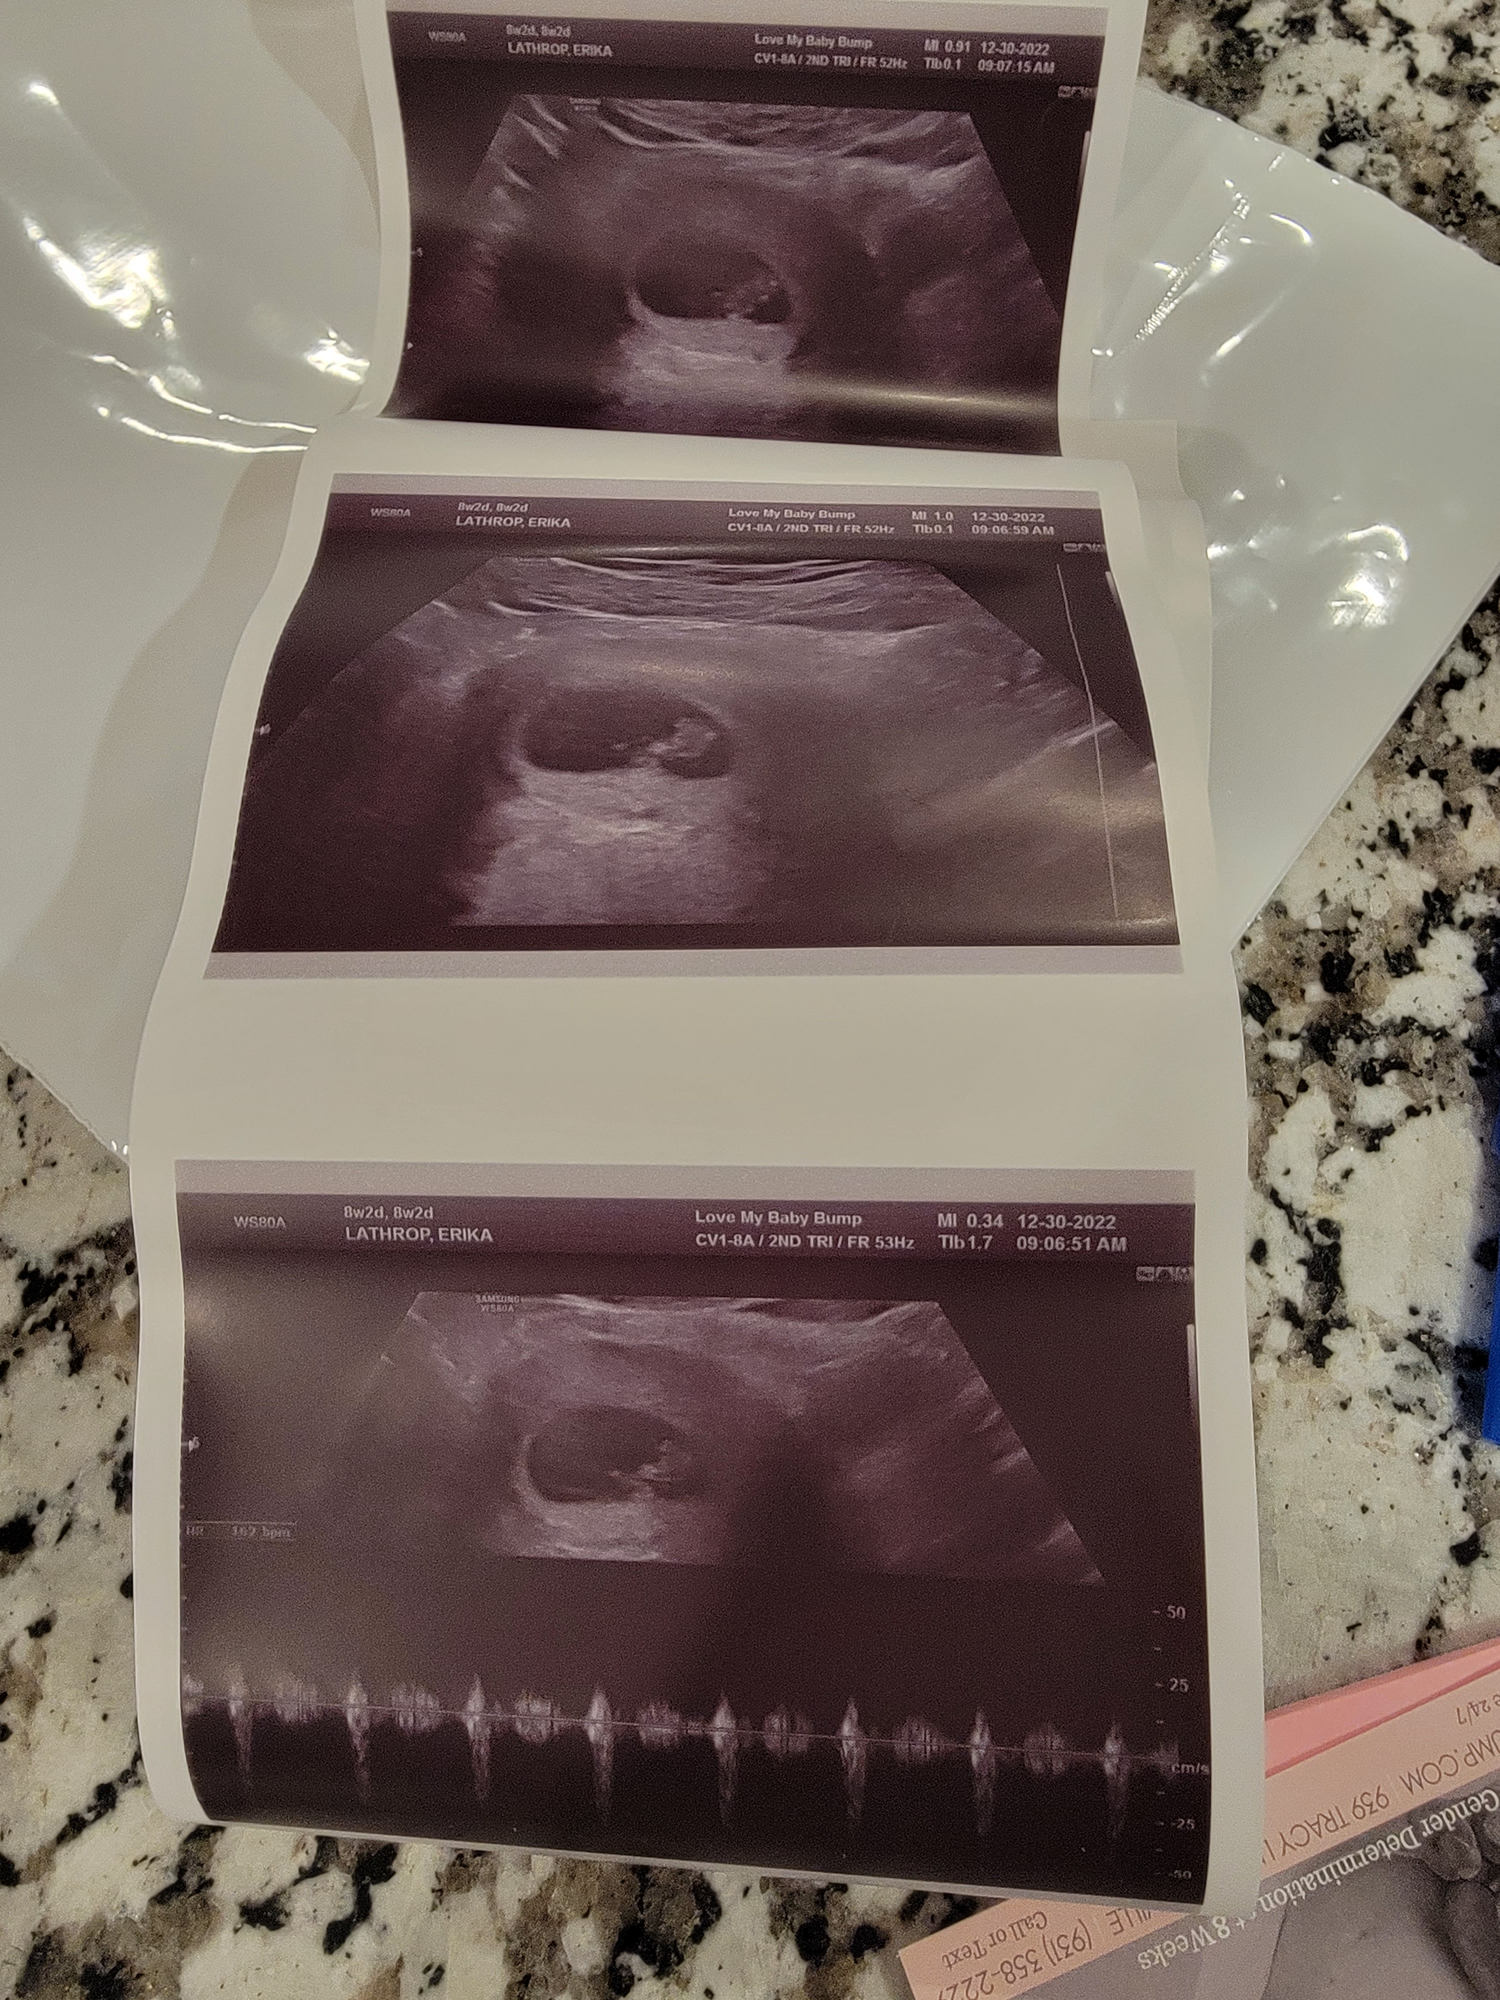

Thought I was 7+3 but measured 8 weeks on 12/23 with heart rate of 169 and lots of movement. Going back tomorrow for follow up U/S given the hazy fluid in the uterus. Amniotic fluid looks fine. OB thought I might have had a small subchorionic bleed. Anyone who’s had this experience please let me know.

First ultrasound went well, I almost cried from relief. Baby is measuring 8+2 so due date has been adjusted to 8/16. Heart rate 176. Pic of the little bean attached.